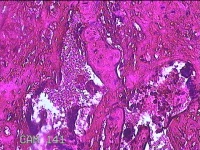

子宫腔内容物

性别

女

年龄

33岁

临床诊断

异常子宫出血;药流不全?宫腔占位

一般病史

阴道流血9天。

标本名称

大体所见

灰白暗红色不规则碎组织1.5x1x0.3cm一堆,未发现明显的绒毛样组织。

不具诊断价值。